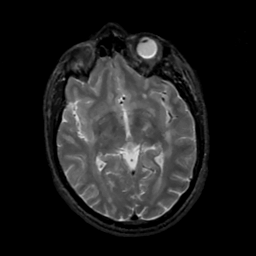

MR Study #5, March 10, 1991 -- Slice #25